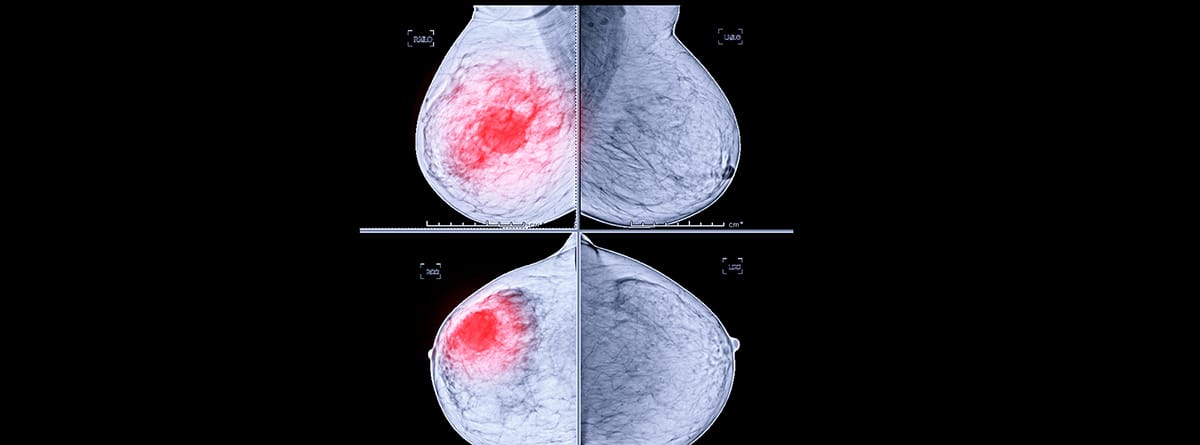

La mamografía es una técnica radiológica que explora las mamas en su máxima extensión. Para lograr las mejores imágenes se coloca la mama entre dos placas de metacrilato que tienen la finalidad de comprimir la mama para extender al máximo el tejido e inmovilizarlo para que la imagen sea lo más nítida posible. Una vez el técnico de radiología ha colocado las mamas en la posición adecuada se proyectará una baja dosis de rayos X sobre las mamas, que atravesarán todo su grosor componiendo una imagen que será revisada exhaustivamente por el radiólogo para poder identificar lesiones patológicas.

Para informar el resultado de la mamografía el mismo Colegio Americano de Radiología clasificó las mamografías en cinco categorías. Esta clasificación se llama BI-RAD (por sus siglas en inglés Breast Imaging Reporting and Data System), que significa Sistema de datos y notificación de imágenes mamarias. Según la cual hay seis tipos de dictamen en un informe mamográfico:

- BIRADS 0: no concluyente, hace falta realizar alguna prueba de imagen adicional.

- BIRADS 1: mama normal. No hay ningún hallazgo a describir, ni hacen falta pruebas adicionales y se emplaza a realizar el nuevo control de cribado en el plazo que se determine por edad.

- BIRADS 2: mama diagnosticada como normal, sin sospecha, pero en la que se describen hallazgos benignos, como quistes, ganglios intramamarios o nódulos de aspecto benigno. La actitud es seguir controles habituales por edad.

- BI-RADS 3: mama con hallazgos probablemente benignos, pero que generan más duda que la categoría 2, para lo cual hay que realizar estudios adicionales (punción, biopsia…) o control semestral.

- BI-RADS 4: lesión probablemente maligna, que requiere estudio inmediato y que tendrá un valor predictivo positivo para cáncer entre un 30 y un 70%.

- BI-RADS 5: lesión altamente sugestiva de malignidad, con un valor predictivo positivo para cáncer superior al 70%. Se requiere también estudio inmediato.

- BI-RADS 6: malignidad confirmada por biopsia antes del tratamiento definitivo.

Esta clasificación se usa universalmente para hablar el mismo idioma radiológico en cualquier lugar del mundo con la intención de uniformizar los diagnósticos de las mamografías y estandarizar la conducta a seguir.